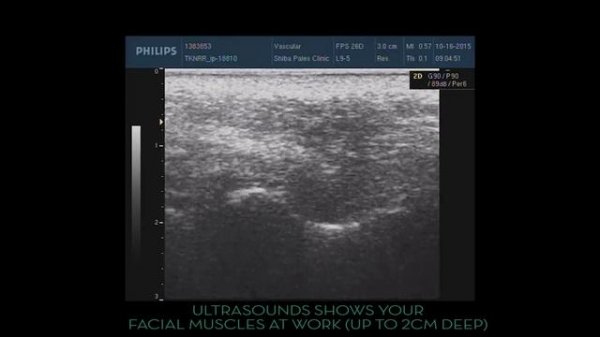

PureLift-ULTRASOUND